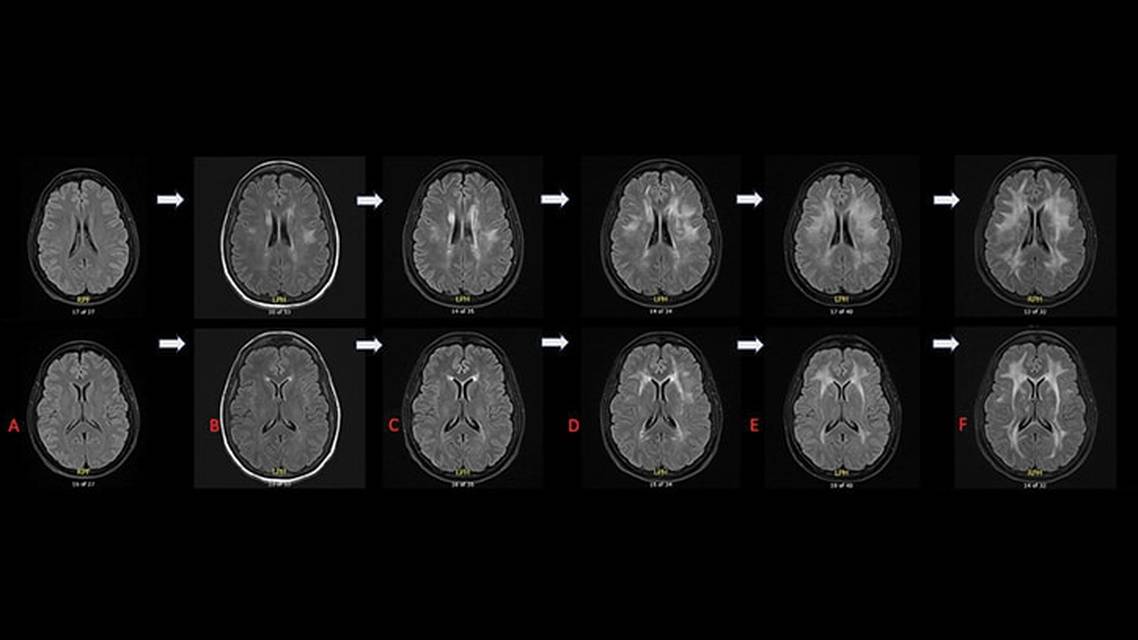

The symptoms continued to progress. Four months later, brain MRI was repeated and showed substantial progression of the confluent and patchy T2/fluid-attenuated inversion recovery (FLAIR) hyperintense signal involving the subcortical, deep, and periventricular white matter, which was most pronounced at the bilateral frontoparietal lobes, without associated enhancement. Spine MRI results remained unchanged. Neuropsychologic testing showed evidence of a moderate cognitive disorder with a cognitive profile of bihemispheric deficits with frontal and subcortical involvement. Psychiatric comorbidities of depression and anxiety were noted. This led to reevaluation of the diagnosis of MS.

EM underwent genetic testing with the Invitae Leukodystrophy and Genetic Leukoencephalopathy Panel and the Add-on Adult-onset Leukodystrophy and Leukoencephalopathy Panel (Invitae, San Francisco, CA). The results were uncertain, with 11 variants of uncertain significance identified. Because of the broad differential diagnosis, the decision was made to start immunotherapy; however, while awaiting approval, EM’s condition worsened. Repeat brain MRI showed further progression of severe, diffuse, and confluent white matter signal abnormalities of the cerebral white matter (Figure). Treatment was not initiated due to the emergence of an alternative diagnosis.

The clinical features were nonspecific in this case, making the brain MRI the most important diagnostic tool to suggest a white matter disease. The MRI pattern of diffuse symmetric patchy foci of hyperintense signal within the periventricular, deep, and subcortical white matter of the frontoparietal lobes was similar to findings previously described in POLR3-related leukodystrophy caused by POLR3A or POLR3B variants.4

Another interesting feature of this case is the presence of normal brain MRI results 8 months before presentation and the extent of the progression of demyelinating changes in repeat interval MRI scans at 6 and 12 months later, which is unusual for a genetic condition. The diagnosis of this condition can be challenging when initial clinical and radiographic findings overlap with acquired demyelinating disease.